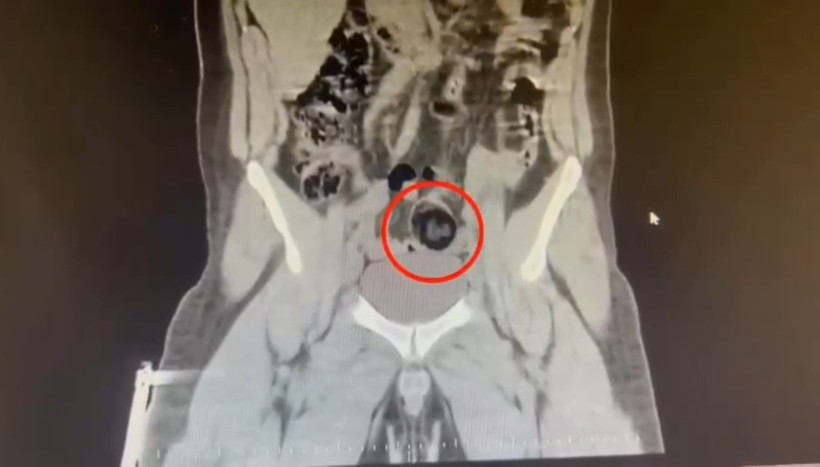

Kars Harakani Devlet Hastanesi'ne götürülen F.H.'nin çekilen röntgeninde, makatında uyuşturucu tespit edildi. 105,98 gram metamfetamin, cerrahi operasyonla çıkarıldı. Emniyetteki işlemlerinin ardından adliyeye sevk edilen şüpheli, çıkarıldığı hakimlik tarafından tutuklandı.